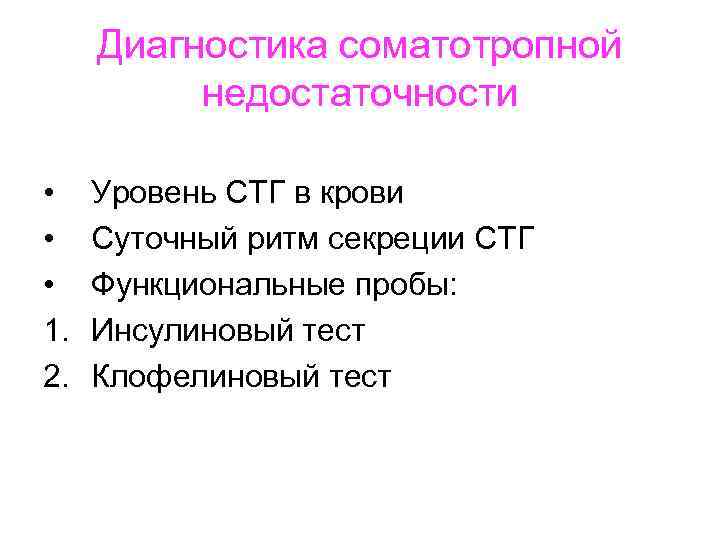

Диагностика соматотропной недостаточности • • • 1. 2. Уровень СТГ в крови Суточный ритм секреции СТГ Функциональные пробы: Инсулиновый тест Клофелиновый тест

Диагностика соматотропной недостаточности • • • 1. 2. Уровень СТГ в крови Суточный ритм секреции СТГ Функциональные пробы: Инсулиновый тест Клофелиновый тест